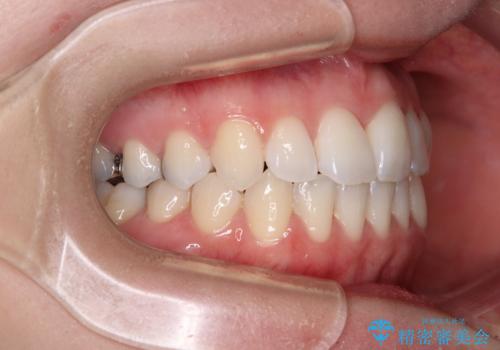

急速拡大装置により骨格はある程度改善されましたが、奥歯の咬み合わせ改善に非常に時間がかかってしまいました。

デコボコを改善させるだけでなく、しっかりとした咬合状態を獲得することができ、患者様には大変満足していただけました。